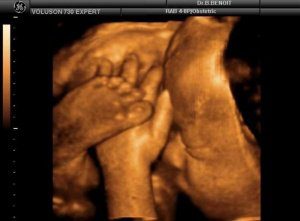

узи 41 неделя